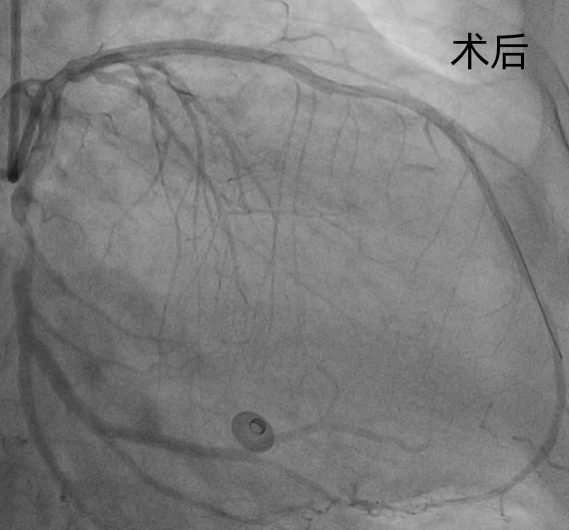

钟先生抵达医院后,直接送入导管室,冠脉造影清晰显示:前降支(LAD)近端完全闭塞,远端血流中断,心肌正处于“断供”坏死的危急状态。

心血管科团队当机立断,迅速实施PCI术,精准植入3枚支架,闭塞血管瞬间恢复通畅。从患者入院到血管成功开通,全程仅用46分钟,远优于国际指南60分钟的标准。